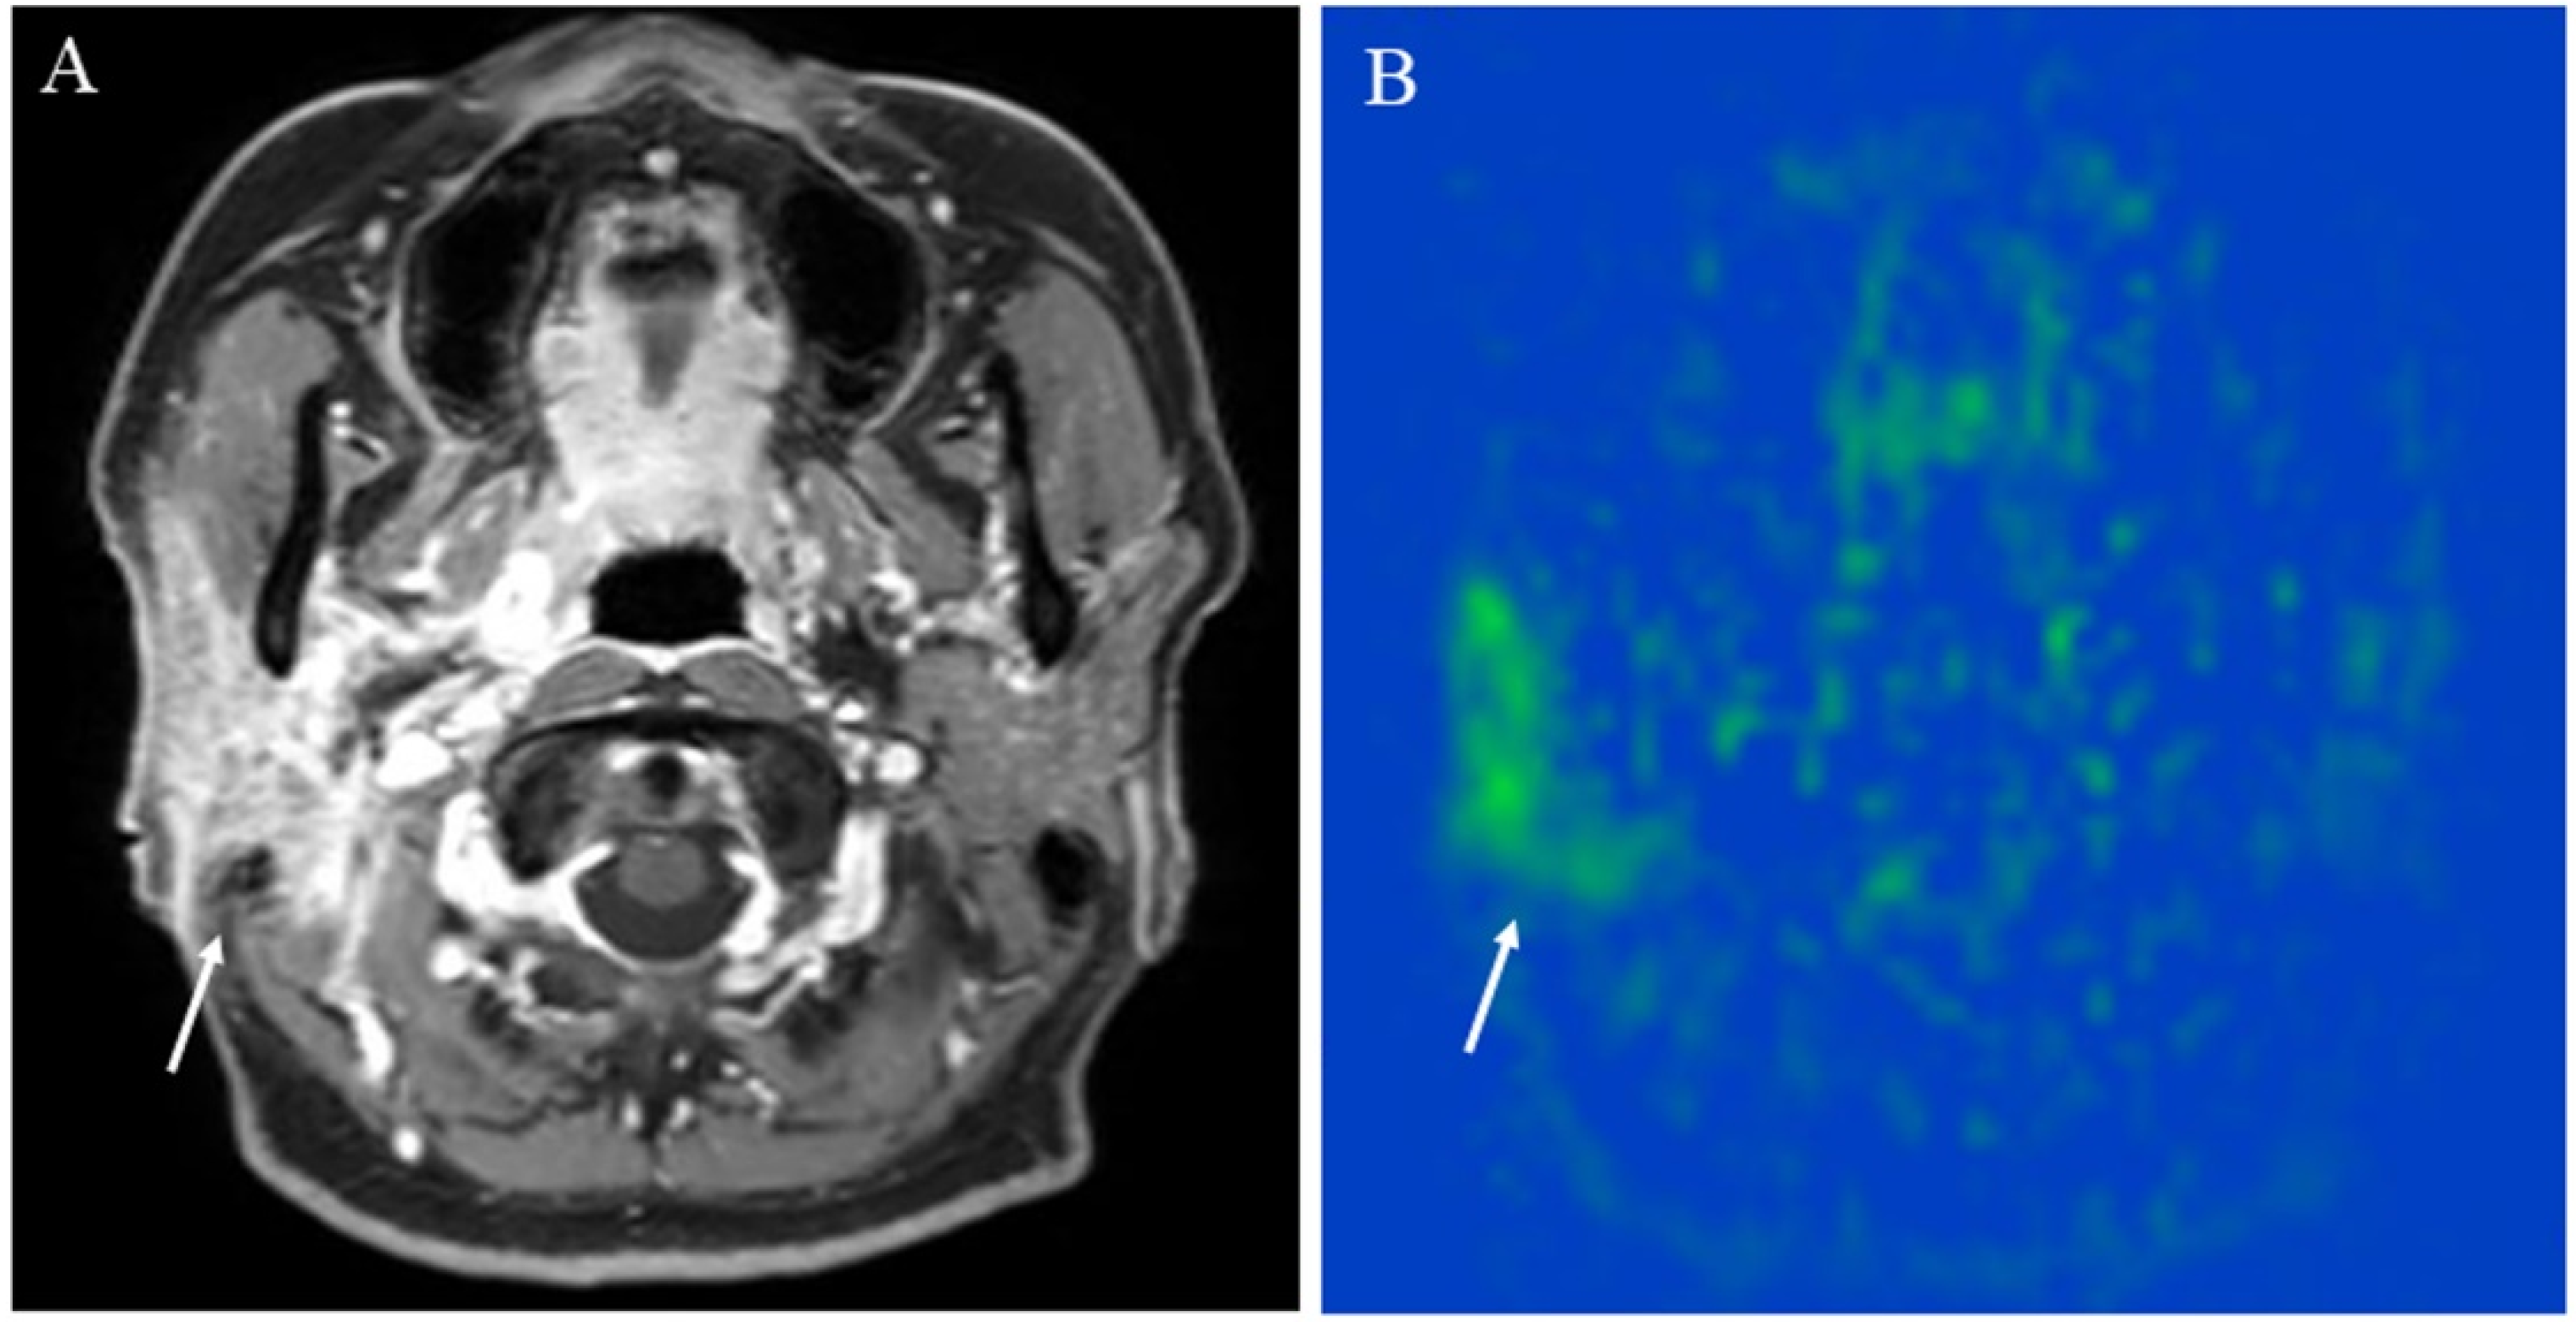

Figure 5. A 43-year-old female with immunoglobulin G4-related disease that involves the bilateral lacrimal gland: (A) Short tau inversion recovery (STIR) shows bilaterally enlarged lacrimal glands with high signal intensity (arrows); (B) pCASL image shows high blood flow within the lesions (arrows) (right mean of 65.70 mL/100 g/min and left mean of 66.98 mL/100 g/min).